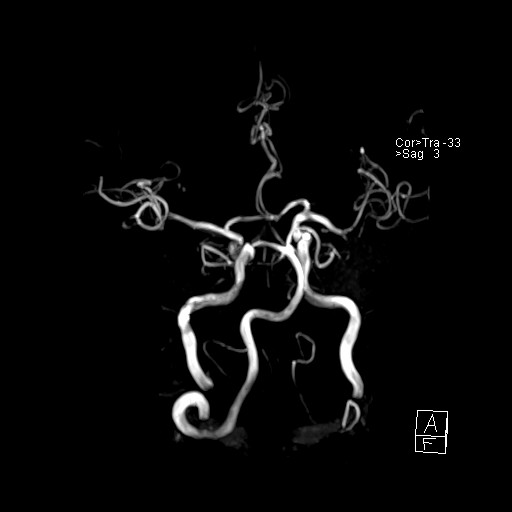

239716 - VILLANUEVA, WILLIAM A. - Number 2 |

|

239716 - VILLANUEVA, WILLIAM A. - Number 2 |